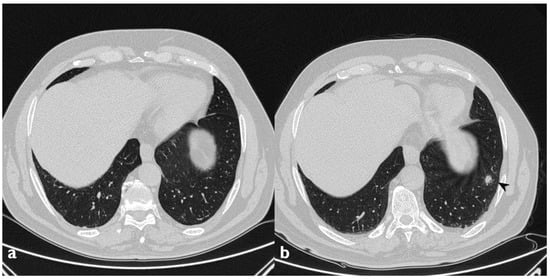

Figure 16. Fibrosing evolution. On the left (a): baseline HRCT. On the right (b): HRCT after 11 months of steroid therapy; new signs of fibrosis-sub-pleural basal reticulations and architectural distortion (arrowheads).

3.8. Evolution and Clinical Outcome

Two patients developed a fibrosing pattern despite the therapy (Figure 16). In more detail, in these two cases, we have observed multiple consolidations and ground-glass opacities at the beginning, with the partial resolution of these findings at follow-up HRCTs (the disappearance of ground-glass opacities and partial reduction of consolidations); however, they developed fibrotic changes like basal reticulations, bronchiectasis and fibrotic striae. Twenty-one patients (95.4%) received steroid therapy (oral corticosteroid, OCS) during the observation period of the study, and 17 of them had regression of radiological findings. Two patients had significant relapse after reducing/interrupting therapy (Table 11); both of them showed a typical consolidative picture at baseline. In one patient, relapse was characterized by the increase in multiple consolidations, particularly in the left lower lobe. This patient presented dry cough, dyspnea, crackles and inspiratory squawks, particularly in the left lower lobe. SpO2 level was 98%. In the other patient, the relapse was characterized by the appearance of multiple consolidations with air bronchogram. This patient presented exertional dyspnea, productive cough and important asthenia. SpO2 level was 98%. One patient refused steroid therapy and was followed up without any immunosuppressive therapy; for this patient, we did not observe any significant deterioration of functional data and radiological features.